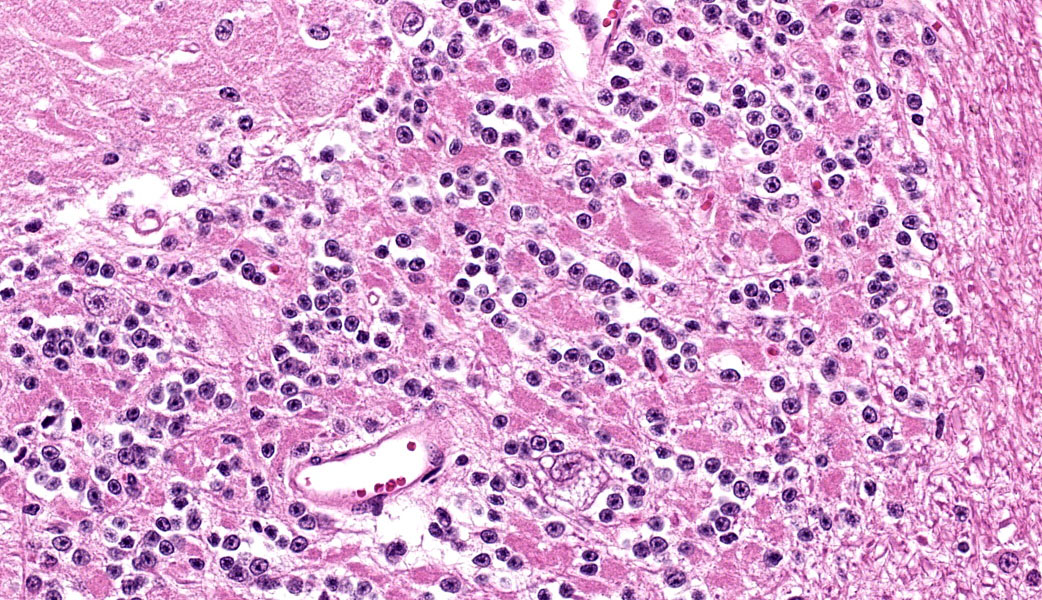

Cerebellum: Multifocally, numerous Purkinje cells at the junction between the molecular and granule cell layer, as well as occasional neurons within the granular cell layer and cerebellar deep nuclei are moderately swollen, have pale granular eosinophilic to clear, finely vacuolated or foamy cytoplasm that often dis-places the nuclei towards the periphery. Neurons are multifocally lost within the Purkinje (empty baskets) and granular layers. Through-out the white matter tracts, there are numerous variably sized (up to 60 μmin diameter) hypereosinophilic axonal swellings (spheroids) as well as less frequent dilation of periaxonal spaces containing fragmented myelin debris (ellipsoids) and foamy macrophages (digestion chambers). Multifocally, few axonal swellings are also present within the granule cell layer (torpedoes).

Cerebellum: Neuronal vacuolation and loss, diffuse, severe with occasional neuronal intracellular granular eosinophilic material ac-cumulation, torpedoes, spheroids and digestion chambers (Wallerian degeneration).

Individuals affected with alpha-mannosidosis are deficient in lysosomal alpha-mannosidase activity, leading to accumulation and storage of mannose within vacuoles of affected cells.3 Under light microscopy, these vacuoles are empty and expand the cytoplasm.16 The con-dition affects all cells within the body except hepatocytes, though is generally most noticeable microscopically within the nervous sys-tem.3 In this case, neuronal vacuolation was most prominent within the thalamus and in Purkinje cells of the cerebellum. Few renal tubular epithelial cells were also affected. In addition to neuronal vacuolation, dysfunction and death of neurons has led to other secondary changes such as Wallerian degeneration with prominent spheroid formation, as well as torpedoes.

Cerebellum: Neuronal vacuolation and loss, chronic, diffuse, severe, with axonal swelling.

The JPC’s morphologic diagnosis for this case made use of the term “axonal swelling” to encompass the torpedoes, spheroids, and diges-tion chambers seen histologically, as all three of these are variations of axonal swelling at different portions of the neuron. Torpedoes are proximal swellings seen within the Purkinje and granular cell layers of the cerebellum; spheroids are swellings at the distal portions of the axons. Digestion chambers are the result of these swellings, where the axons are under-going Wallerian degeneration and are fragmenting. The JPC acknowledged that it is not wrong to list these things out individually. Participants simply chose to group them for the sake of brevity.